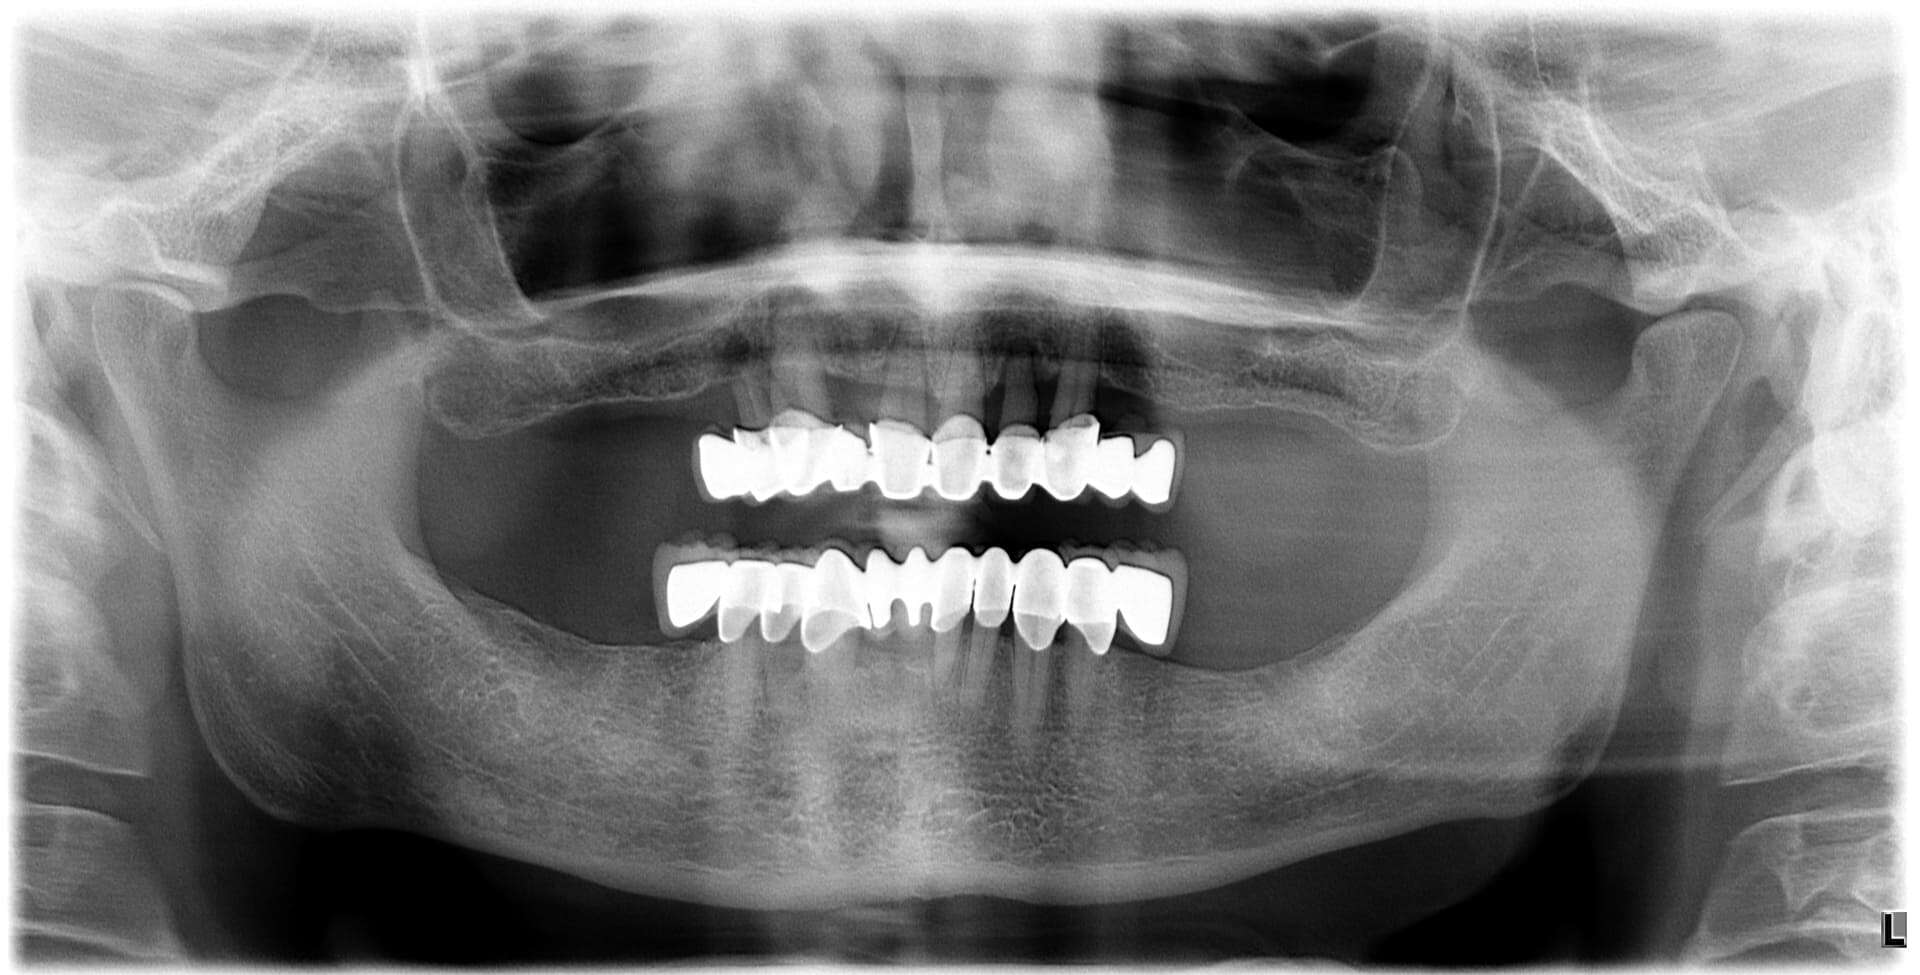

Paziente 1

< Prima

Dopo >